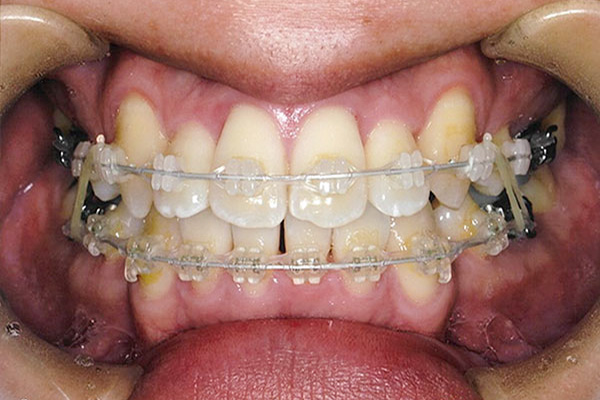

治療前